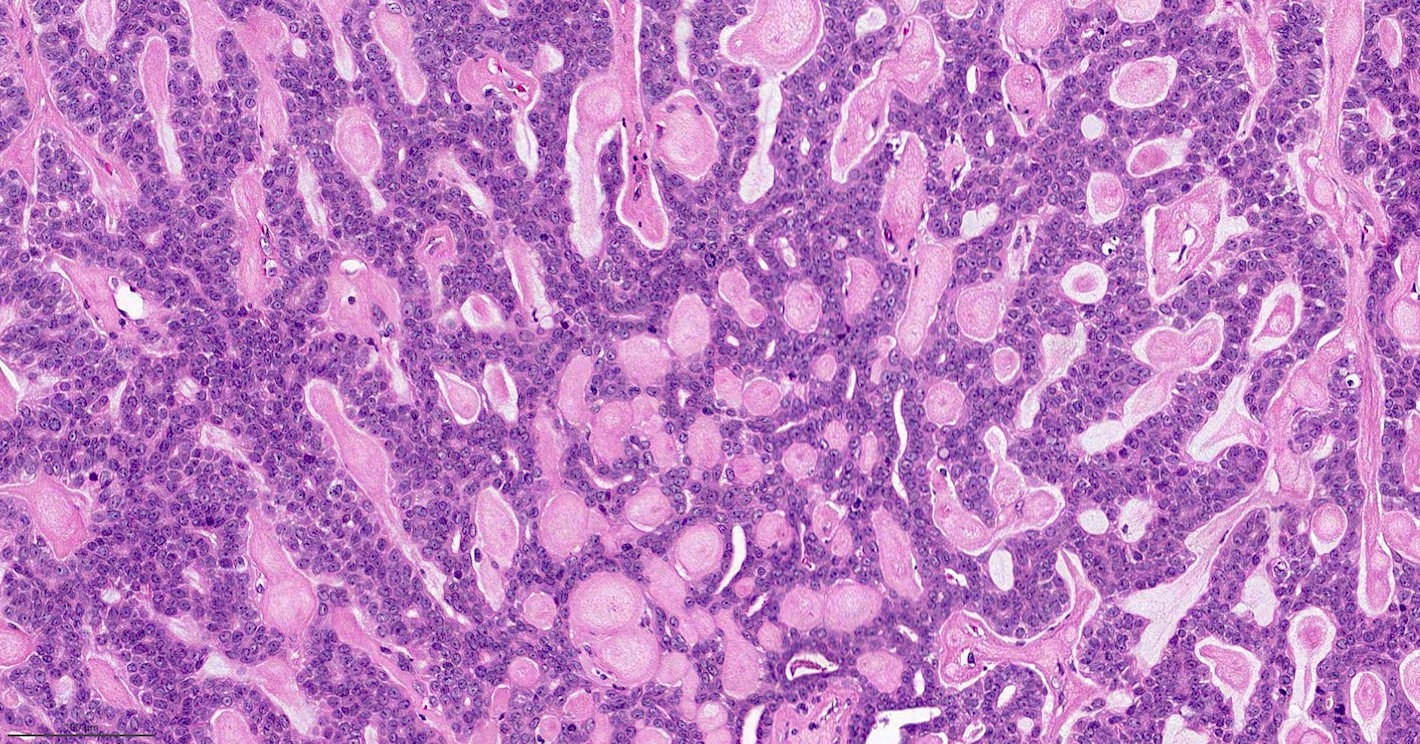

Malignant Adenomyoepithelioma Breast . Adenomyoepithelioma (ame) of the breast is a very rare tumor and is generally considered to be benign. Benign to low grade malignant behavior and a propensity for recurrence. Malignant adenomyoepithelioma (mame) of the breast is an extremely rare breast malignancy, in which they. Adenomyoepithelioma of the breast is an uncommon tumor characterized by dual differentiation into luminal cells and myoepithelial cells. Adenomyoepithelioma (ame) of the breast is a very rare tumor and is generally considered to be benign. Biphasic tumor with epithelial and myoepithelial components. Adenomyoepithelioma (ame) of the breast is a rare disease characterized by a bicellular pattern consisting of both ductal and myoepithelial cells [1, 2].

Pathology Outlines Adenomyoepithelioma & malignant adenomyoepithelioma Malignant Adenomyoepithelioma Breast Biphasic tumor with epithelial and myoepithelial components. Adenomyoepithelioma (ame) of the breast is a rare disease characterized by a bicellular pattern consisting of both ductal and myoepithelial cells [1, 2]. Adenomyoepithelioma (ame) of the breast is a very rare tumor and is generally considered to be benign. Adenomyoepithelioma (ame) of the breast is a very rare tumor and is generally. Malignant Adenomyoepithelioma Breast.